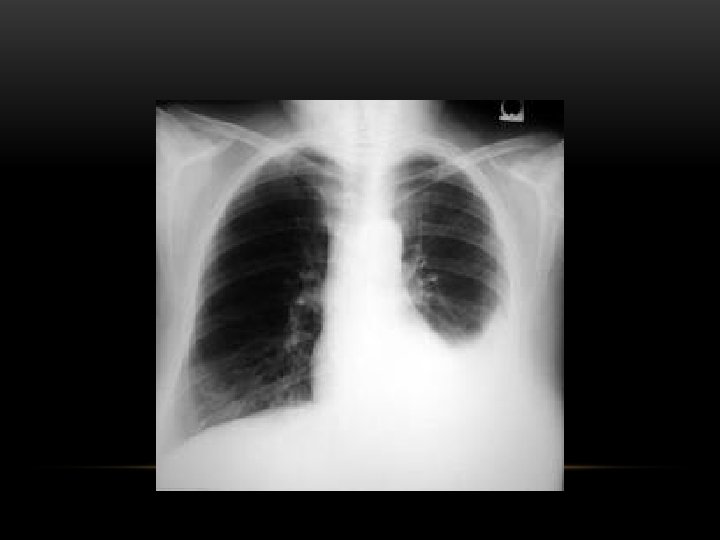

Pleural Fibrosis Diffuse haziness Apical cap thickening Blunting of costophrenic angle Loss of lung volume

Pleural Fibrosis • Small right hemithorax • Diffuse haziness • Blunted costophrenic angle